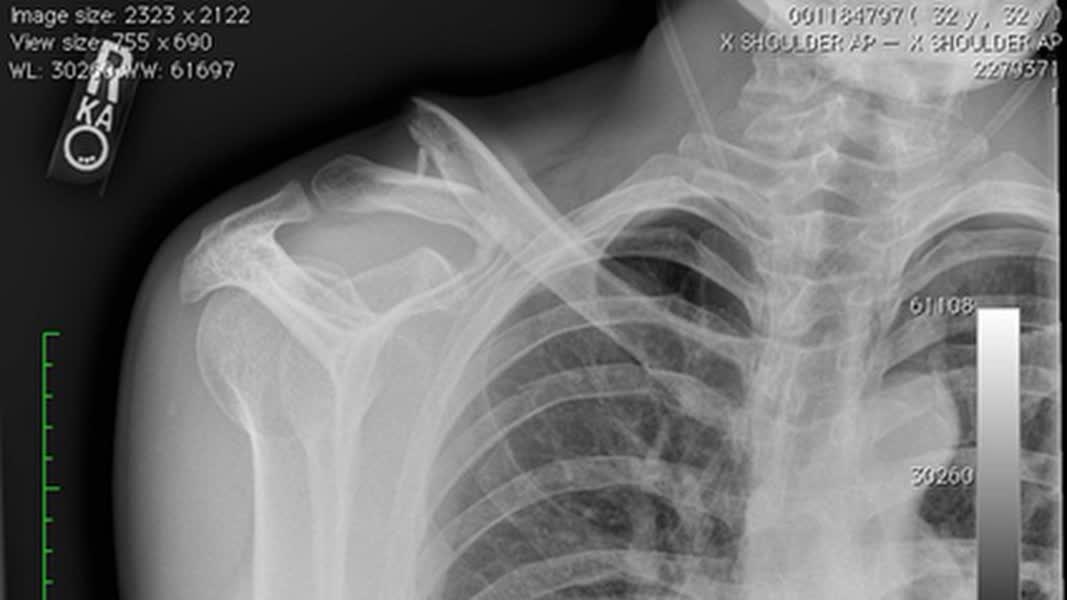

De renner van Lotto-Jumbo kwam tijdens een training in de Verenigde Staten ten val op een slecht deel van de weg, waar ook werkzaamheden waren. Hij brak daarbij zijn sleutelbeen en twee ribben.

Foto: Instagram Robert Gesink